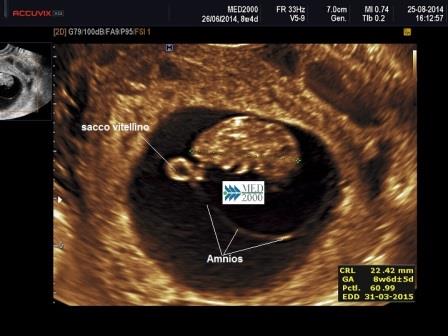

All'ecografia si presenta come un'area cistica tondeggiante, adiacente alla parete della camera gestazionale, identificabile con l'approccio transvaginale già dalla 5a settimana; è possibile distinguere sul contorno le pulsazioni relative alla primitiva circolazione embrionale. Per una visualizzazione ottimale è necessario regolare i parametri della scansione ultrasonografica utilizzando frequenze più alte.

E' generalmente accettato che il sacco vitellino deve essere visualizzato quando il diametro camerale medio è di almeno 8 mm. ( Lyons EA, et al 2005; Tan S, et al. 2012 ).

Le sue dimensioni variano dai 2 mm. a 5 settimane ai 6 mm. a 10 settimane. Valori inferiori a 2 mm. ( Wang XH, et al. 2019 ) o superiori a 6 mm. ( Lindsay DJ, et al. 1992 ) possono indicare una successiva interruzione o una patologica evoluzione della gravidanza; quando non si riesce ad evidenziare l'embrione un sacco vitellino aumentato di dimensioni può essere un indicatore di aborto spontaneo ( Cho FN, et al. 2006 ).